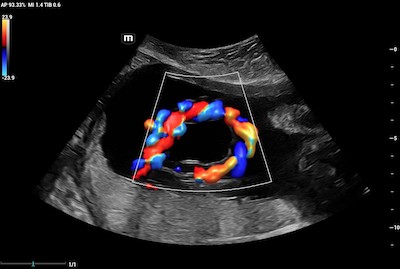

- Heart – Echocardiography utilizes a type of CDI that examines the heart and the velocity of blood flow through the cardiac valves and detects any irregularities between the left and right sides of the heart. CDI of the heart can also determine if there is any blood leakage through the valves.

Color Doppler Imaging of Mitral Valve Dehiscence